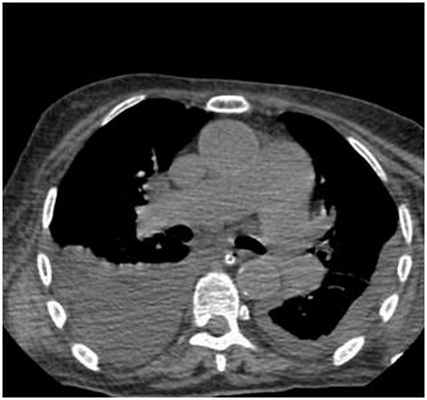

ИНСТРУМЕНТАЛЬНАЯ ДИАГНОСТИКА

К инструментальным методам диагностики в первую очередь относится рентгенография органов грудкой клетки, однако данный метод может быть неинформативным при малых объемах плеврита (до 500 мл), поэтому к дополнительным методам инструментальных исследований относятся УЗИ плевральных полостей и КТ органов грудной клетки.

Двусторонний гидроторакс (компьютерная томография органов грудной клетки)